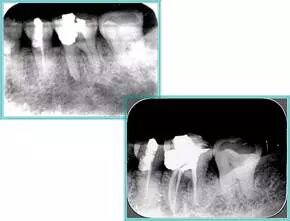

5. 不良根管充填物

常见不良根管充填物有干髓、塑化、塑化 + 根充和不良根充。

牙胶尖什么颜色​牙齿“晓”“技”|最全根管治疗的标准步骤,以及细节把握_https://www.jmylbn.com_新闻资讯_第21张

( 1 )干髓。

干髓治疗时,开髓后髓腔里注入甲醛甲酚 FC 灌髓,三聚甲醛固定,髓室底放置三聚甲醛缓慢释放,进行根管无害化处理。髓腔缓慢坏死,机体代偿出现根管钙化。如果患者在封闭腔出现出现病变,由于髓腔钙化,根管堵塞严重,检查治疗比较困难。

解决方法:1 )彻底去除坏死的牙髓组织。2 )借助化学性药剂,如 EDTA 等。3 )初锉选用8#或10#K 锉,平衡力法探察到工作长度 , H锉上下提拉法使根管扩大,提高工作效率。

牙胶尖什么颜色​牙齿“晓”“技”|最全根管治疗的标准步骤,以及细节把握_https://www.jmylbn.com_新闻资讯_第22张

左图和上图为干髓治疗后牙齿,龋齿疏通后进行根管充填。

( 2 )塑化。

传统的治疗思维:塑化治疗后患者需将塑化液清理干净,达到彻底根管治疗目的。 牙胶尖什么颜色​牙齿“晓”“技”|最全根管治疗的标准步骤,以及细节把握_https://www.jmylbn.com_新闻资讯_第23张

目前的治疗思维:以前塑化治疗效果好时不必清理干净塑化液。对于根尖没有病变的患者,可借助溶解剂建立通路;根尖存在病变的患者往往是塑化治疗不理想患者,需要彻底打通通路。